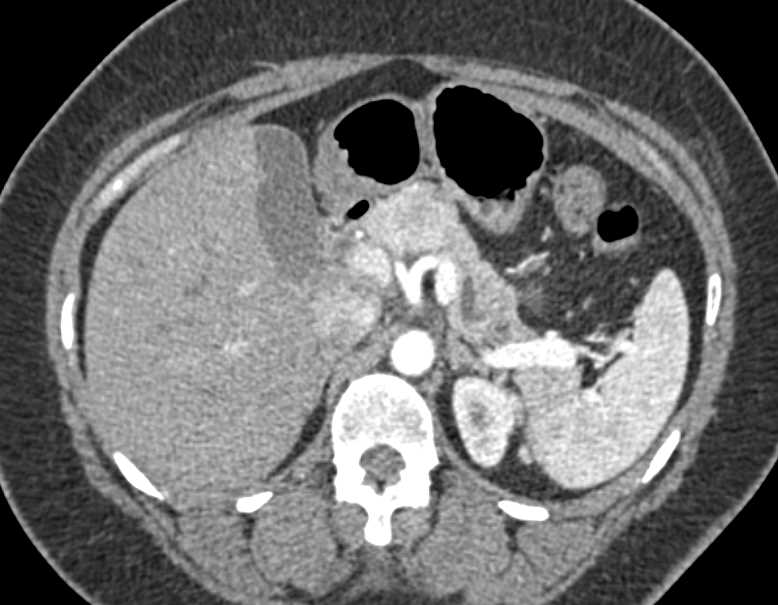

Neuroendocrine Tumor Body of Pancreas